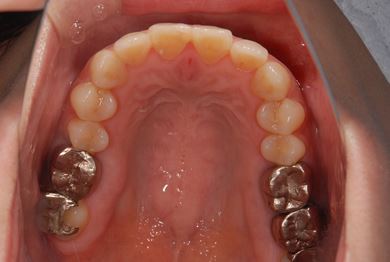

| 性別/年齢 | 女性 / 39歳 | ||||||||||||||||||||||||||||||||

| 主訴 | 右奥歯の虫歯と、右奥のインプラント治療について相談。 | ||||||||||||||||||||||||||||||||

| 治療方針 | 右下奥欠損部分をインプラント治療にて、機能的・審美的回復を行う。 | ||||||||||||||||||||||||||||||||

| 治療内容 | インプラント1本、ハイブリッドセラミッククラウン1本 | ||||||||||||||||||||||||||||||||